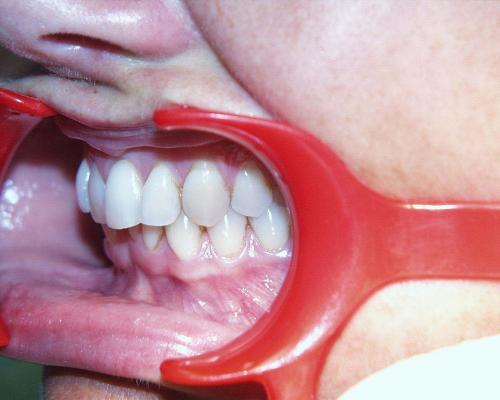

Fallbeispiel 4

Fallbeispiel 4 zeigt einen häufigen Befund bei erwachsenen Patienten: Die Stellung der Schneidezähne hat sich in beiden Zahnbögen im Laufe der Jahre erkennbar verschlechtert, und die Patienten fühlen sich dadurch zunehmend beeinträchtigt. Die in diesem Beispiel nur geringgradigen Abweichungen im Oberkiefer ließen sich mit nahezu unsichtbaren, herausnehmbaren Alignerschienen behandeln, während die Korrektur der stärkeren Schachtelstellung der unteren Frontzähne eine festsitzende Zahnspange erforderte. Auch hier ist nach der Korrektur die Verwendung innenliegender aufgeklebter Stabilisierungsdrähte über viele Jahre hinweg ratsam.

Während der Behandlung